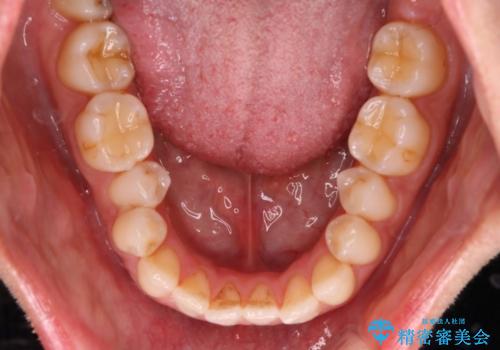

- 拡大・IPRによるスペースゲインを主とした非抜歯・マウスピース矯正を計画しました。

奥歯の位置関係の修正は難儀することが多いマウスピース矯正ですが、割とスムーズに奥歯の位置関係の修正をすることができました。

クロスバイトもきれいになり、きれいな歯並びとなりました。